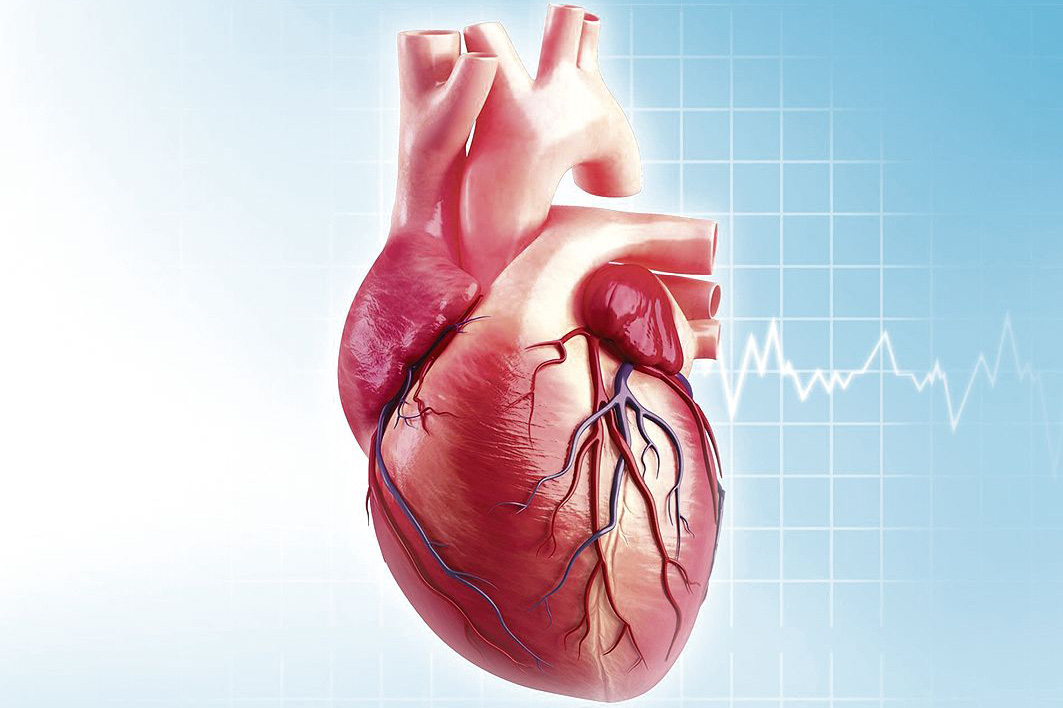

Анатомия здорового сердца: фотографии и иллюстрации